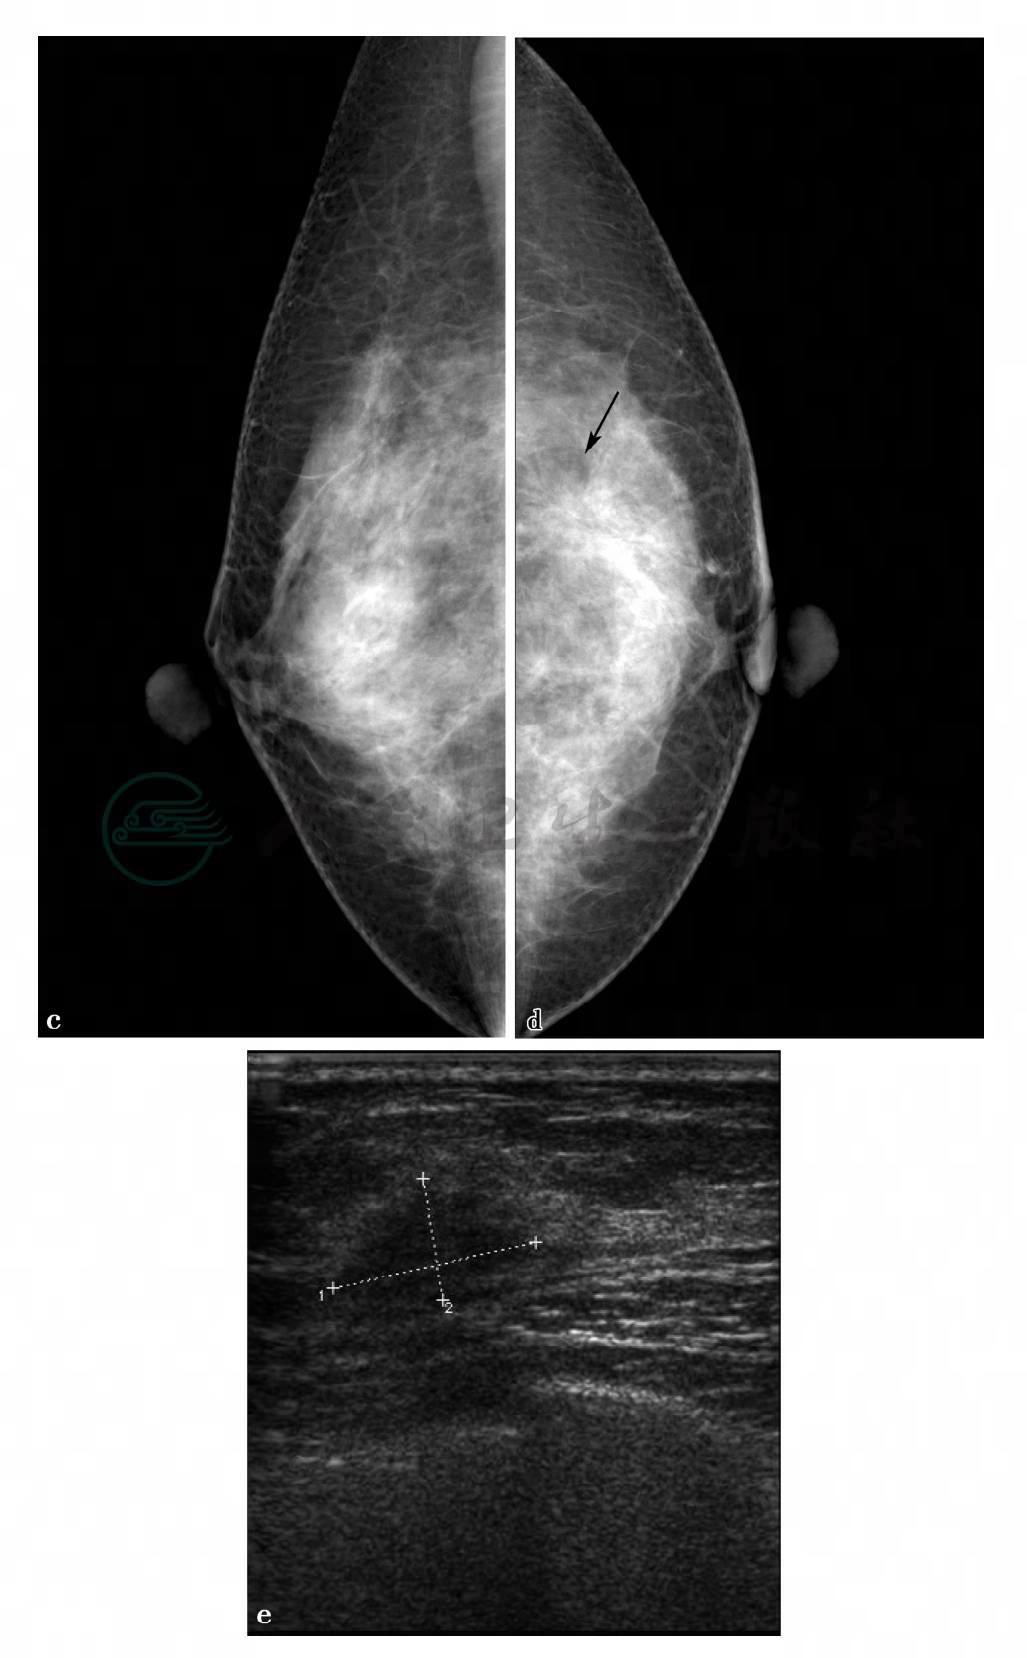

MRI平扫及增强扫描。

图2 图2f~i,分别为MRI动态增强前及增强后1min、2min、8min。图2j,病变时间-信号强度曲线图。图2h,病变DWI图(b= 1000s/mm2)。图2l,MIP图。图2g~i,MRI显示左乳腺中上方局限不规则异常强化,边界不清,范围约1.2cm×2.2cm× 2.5cm。图2j,动态增强后病变时间-信号强度曲线呈流出型。图2h、l,DWI上呈高信号,ADC值较低,病变邻近血管较丰富,皮下脂肪层混浊